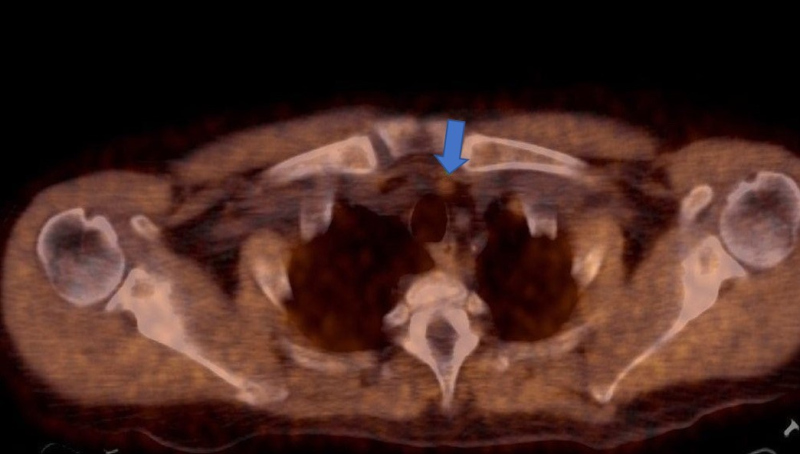

A raíz del hallazgo tomográfico y por sospecha de patología oncológica se solicita PET- CT con fluorodesoxiglucosa (18F-FDG), donde se advierten múltiples lesiones óseas líticas hipermetabólicas (algunas con erosión de la cortical), incluyendo un foco esternal con SUV máx. 8,4, otra en el 7° arco costal derecho (fig. 1) y una tercera imagen focal con insuflación cortical, densidad en vidrio esmerilado en su interior ubicada en tercio medio femoral (fig. 2, arriba), con algunos otros focos hipermetabólicos sin traducción tomográfica. También se evidencia a nivel submaxilar derecho una lesión con densidad de partes blandas, con captación aumentada (SUV máx. 4,2) y centro fotopénico en relación a necrosis.

La 18F-FDG es un radiotrazador que permite analizar el metabolismo energético de la lesión en estudio; representa un marcador imagenológico inespecífico, ya que puede ser captado con tanta avidez por una lesión oncológica como por una patología inflamatoria. Solamente indica aumento de metabolismo de glucosa y no informa sobre su etiología, la cual debe ser valorada en un contexto clínico-morfo-metabólico y certificada con estudio anatomopatológico. (3) En este caso, la interpretación clínica del PET-CT con FDG fue que la formación submaxilar estaba en relación a compromiso inflamatorio/infeccioso derivado del procedimiento quirúrgico odontológico reciente, descartando una posible patología oncológica linfo-proliferativa. Se llegó a la conclusión preliminar de que las lesiones óseas formaban parte de un proceso osteodistrófico debido a la patología renal crónica de base. Esto condujo a la toma de biopsia con confirmación histopatológica de la lesión en el 7° arco costal posterior izquierdo, donde se halló evidencia compatible con tumor pardo (fig. 2, abajo).